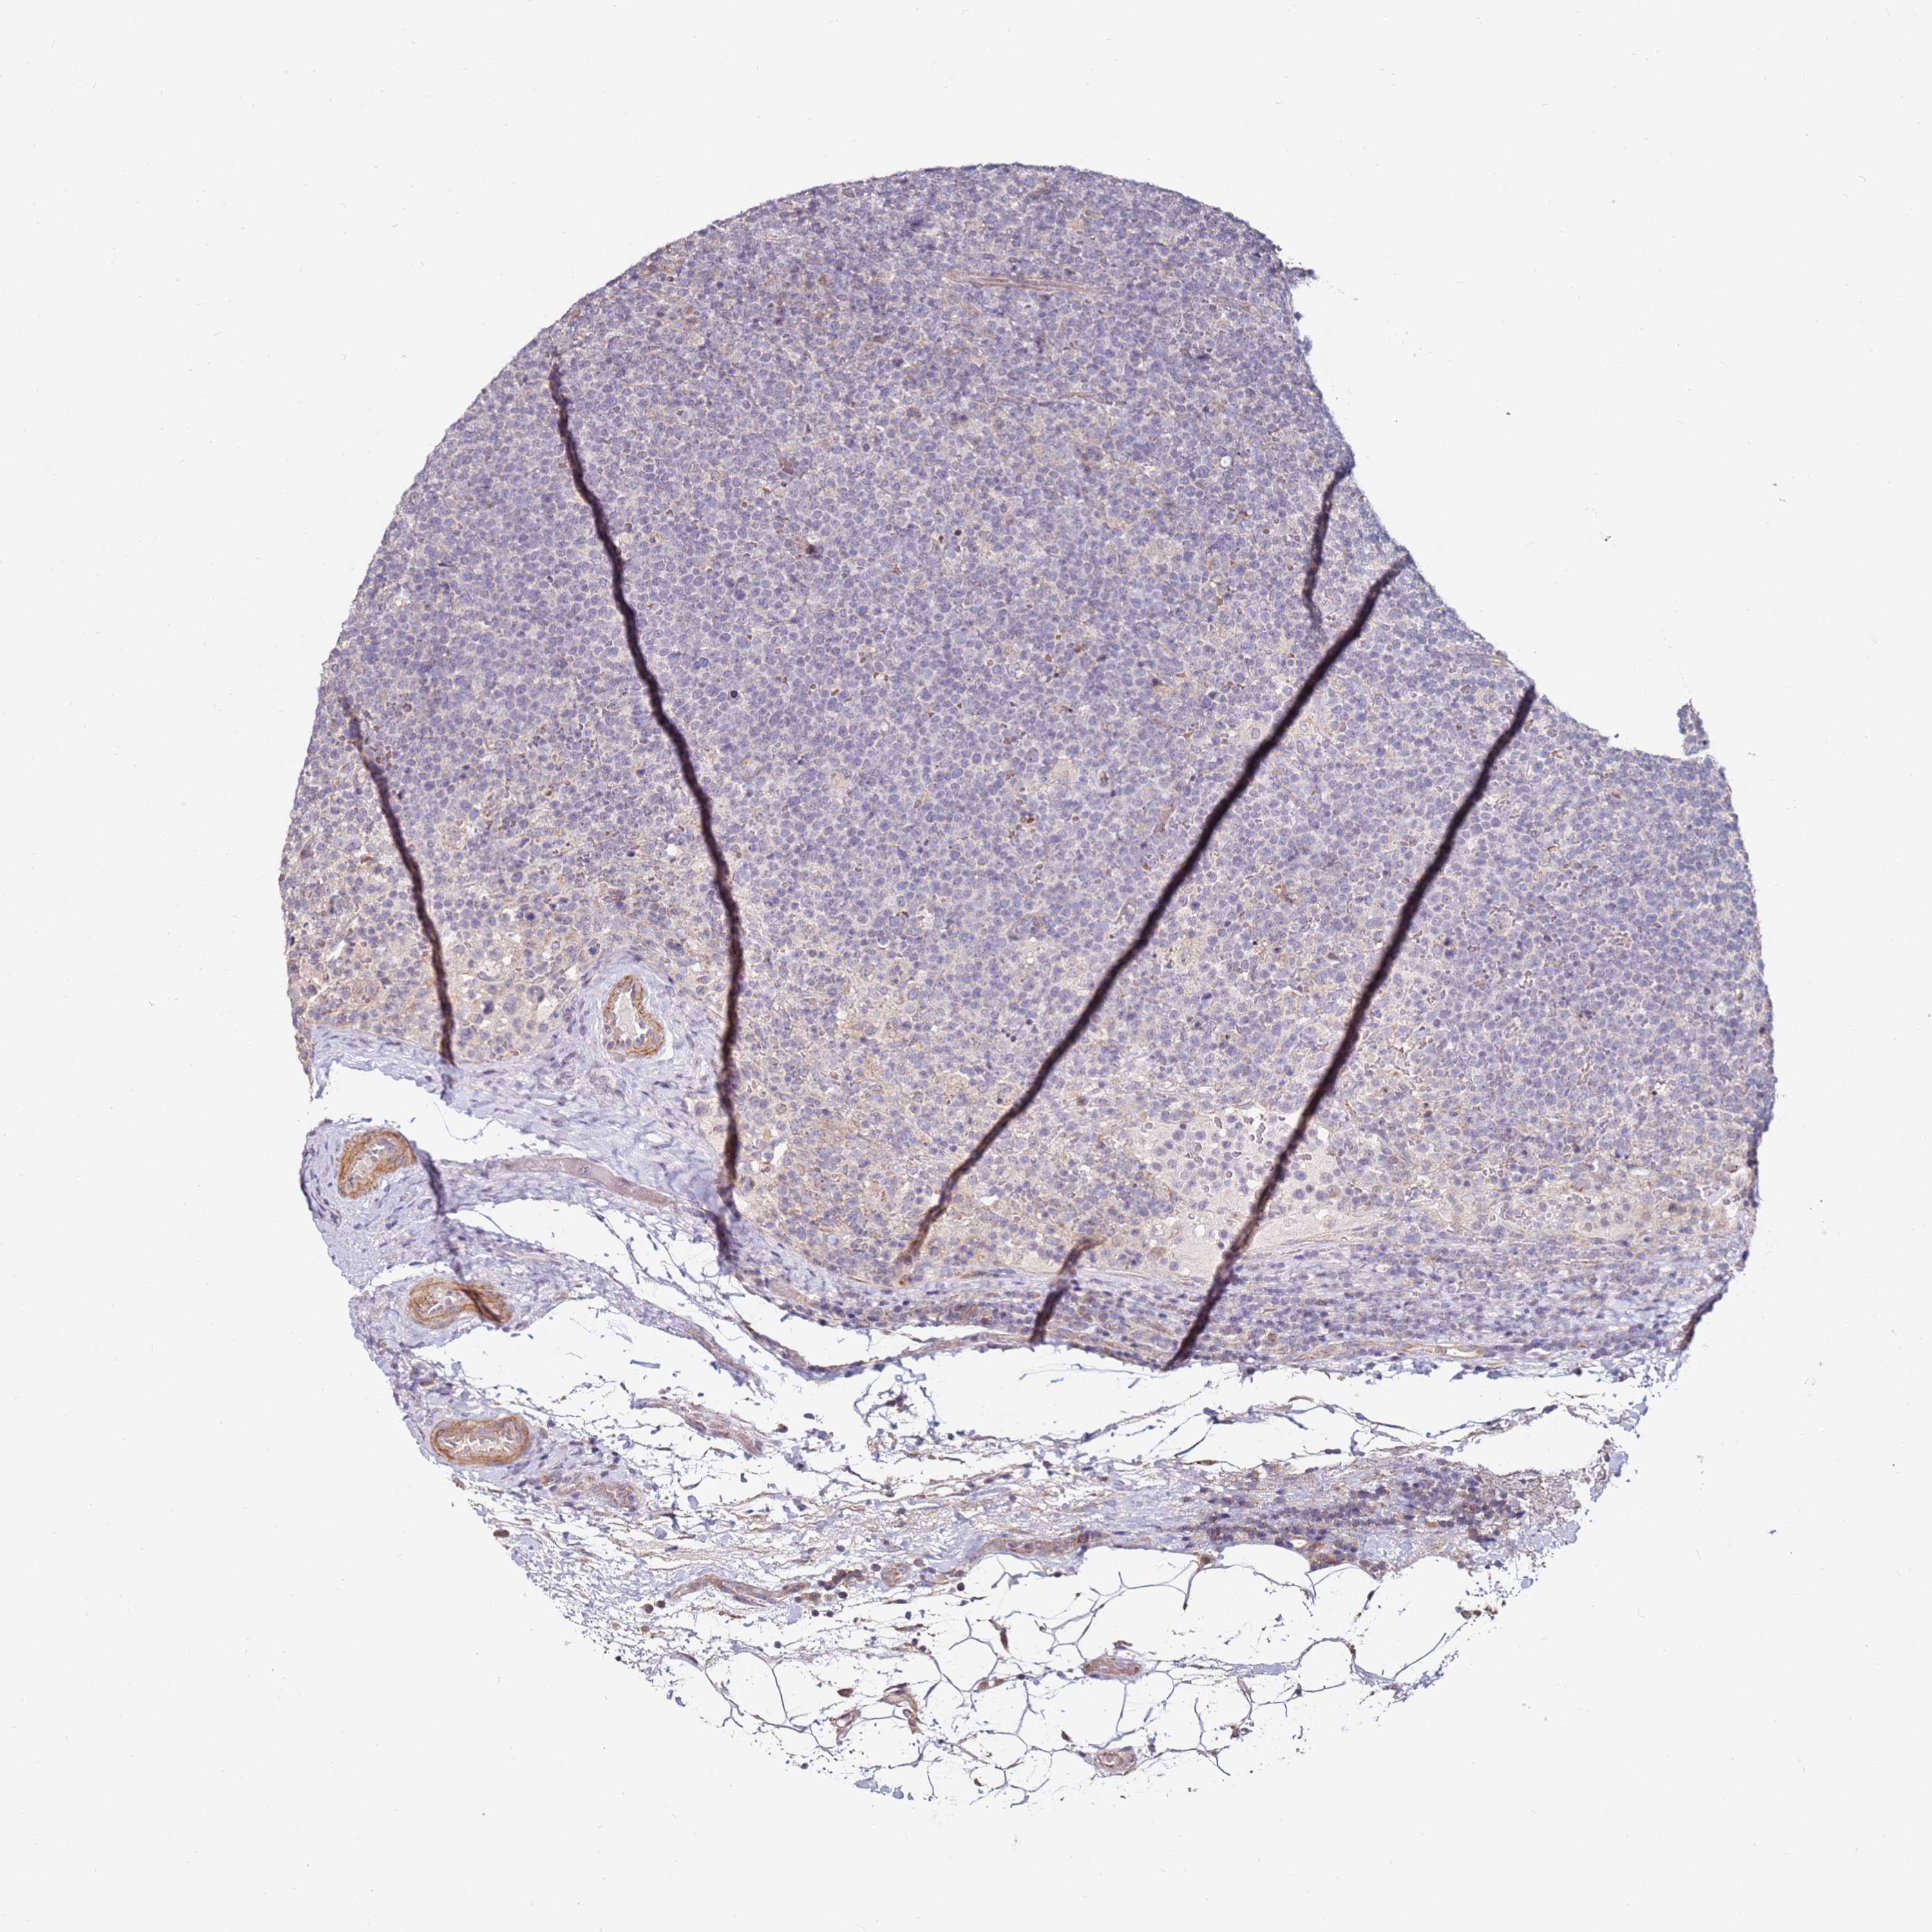

CANCER LYMPHOMA Show tissue menu

LYMPHOMA - Protein expressioni

A mouse-over function shows sample information and annotation data. Click on an image to view it in a full screen mode. Samples can be filtered based on level of antibody staining by selecting one or several of the following categories: high, medium, low and not detected. The assay and annotation is described here.

Each image is clickable and will lead to virtual microscopy that enables deeper exploration of all samples and also displays staining intensity scores, fraction scores and subcellular localization as well as patient and tissue information for each sample.

Antibody HPA039987

Antibody HPA042645

Staining

High

Medium

Low

Not detected

Intensity

Strong

Moderate

Weak

Negative

Quantity

>75%

75%-25%

<25%

None

Location

Nuclear

Cytoplasmic/membranous

Cytoplasmic/membranous,nuclear

Hodgkin's disease, NOS

Malignant lymphoma, non-Hodgkin's type, High grade

Malignant lymphoma, non-Hodgkin's type, Low grade